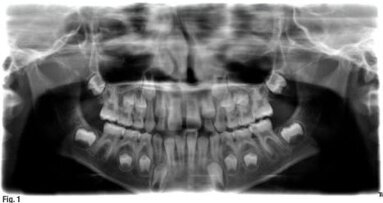

Parmi les conférenciers. Matthias Zehnder (Suisse), Josiane Almeida (Brésil), Ruth Pérez-Alfayate (Espagne) et Antonis Chaniotis (Grèce) interviendront. Le congrès d'endodontie portera sur des sujets tels que l'irrigation et la désinfection des canaux radiculaires, la restauration des dents traitées par endodontie, l'effet de la radiothérapie sur les structures dentaires, la gestion des blocages des canaux radiculaires et la justification de la prise en charge des cas complexes et limites en endodontie.

« L'un de nos orateurs sera le Dr Mitsuhiro Tsukiboshi, qui vient du Japon. L'Association américaine des endodontistes décrit le Dr Tsukiboshi comme « la plus grande autorité mondiale en matière d'autotransplantation de dents » sur son site web. Sa conférence sur l'autotransplantation de dents dans le cadre de plans de traitement complexes est à ne pas manquer », a souligné Stephen Jones.